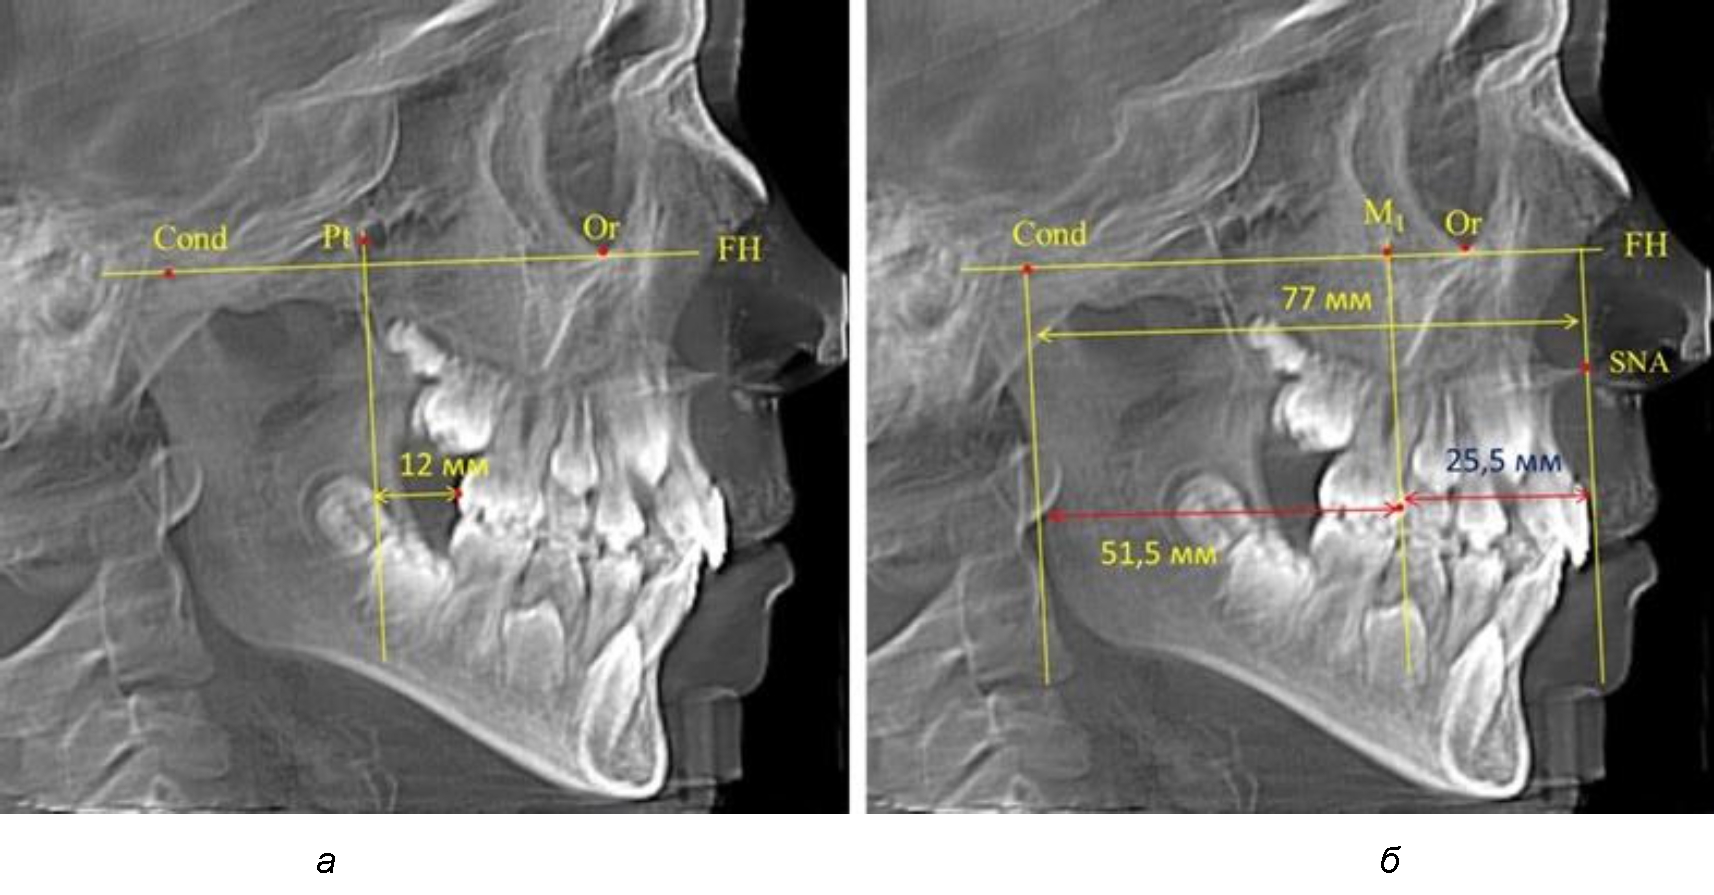

Так, при расстоянии от крыловидной вертикальной плоскости PTV до дистальной поверхности верхнего первого постоянного моляра в 13 мм сагиттальный размер гнатического отдела был 82 мм. При этом отношение кондилярно-спинального расстояния к кондилярно-молярному размеру (54,5) было близким к коэффициенту 1,5, что представлено на рис. 2.

В то же время при увеличенном расстоянии от крыловидной вертикальной плоскости PTV до дистальной поверхности верхнего первого постоянного моляра, равное 23 мм, сагиттальный размер гнатического отдела составил 92 мм. При этом отношение кондилярно-спинального расстояния к кондилярно-молярному размеру (30,5), так же, как и при малых размерах, было близким к коэффициенту 1,5, что представлено на рис. 3.

Рис. 2. Особенности положения первых моляров по R. E. McDonald (а) и по предложенному методу (б) при уменьшенном молярно-крыловидном расстоянии

Рис. 3. Особенности положения первых моляров по R. E. McDonald (а) и по предложенному методу (б) при увеличенном молярно-крыловидном расстоянии

Второй частью исследования был анализ положения первых постоянных моляров в различные периоды сменного прикуса. На телерентгенограммах детей периода прикуса молочных зубов дистальная поверхность зачатка первого постоянного моляра отстояла от крыловидной вертикали на величину, составляющую около 7 мм, что было близким по значению к данным R. E. McDonald. Сагиттальный размер гантического отдела составлял около 60 мм, а его отношение к кондилярно-молярной глубине – 1,5 (рис. 4).

По мере роста челюстей увеличивалась глубина гнатического отдела лица, и кондиллярно-спинальный размер составлял в среднем (74,57 ± 0,93) мм. Дистальная поверхность первого постоянного моляра отстояла от крыловидной вертикали на величину, составляющую около 11 мм, что, так же, как и в периоде прикуса молочных зубов, было близким по значению к данным R. E. McDonald, а именно возраст, плюс 3 мм. Однако величина ошибки среднего значения свидетельствовала о вариабельности признака даже в восьмилетнем возрасте после замены передней группы зубов и установки ключевых постоянных моляров в окклюзионное равновесие. Обращает на себя внимание отношение глубины гнатического отдела лица к дистальному отделу, а именно к кондилярно-молярному расстоянию (рис. 5).